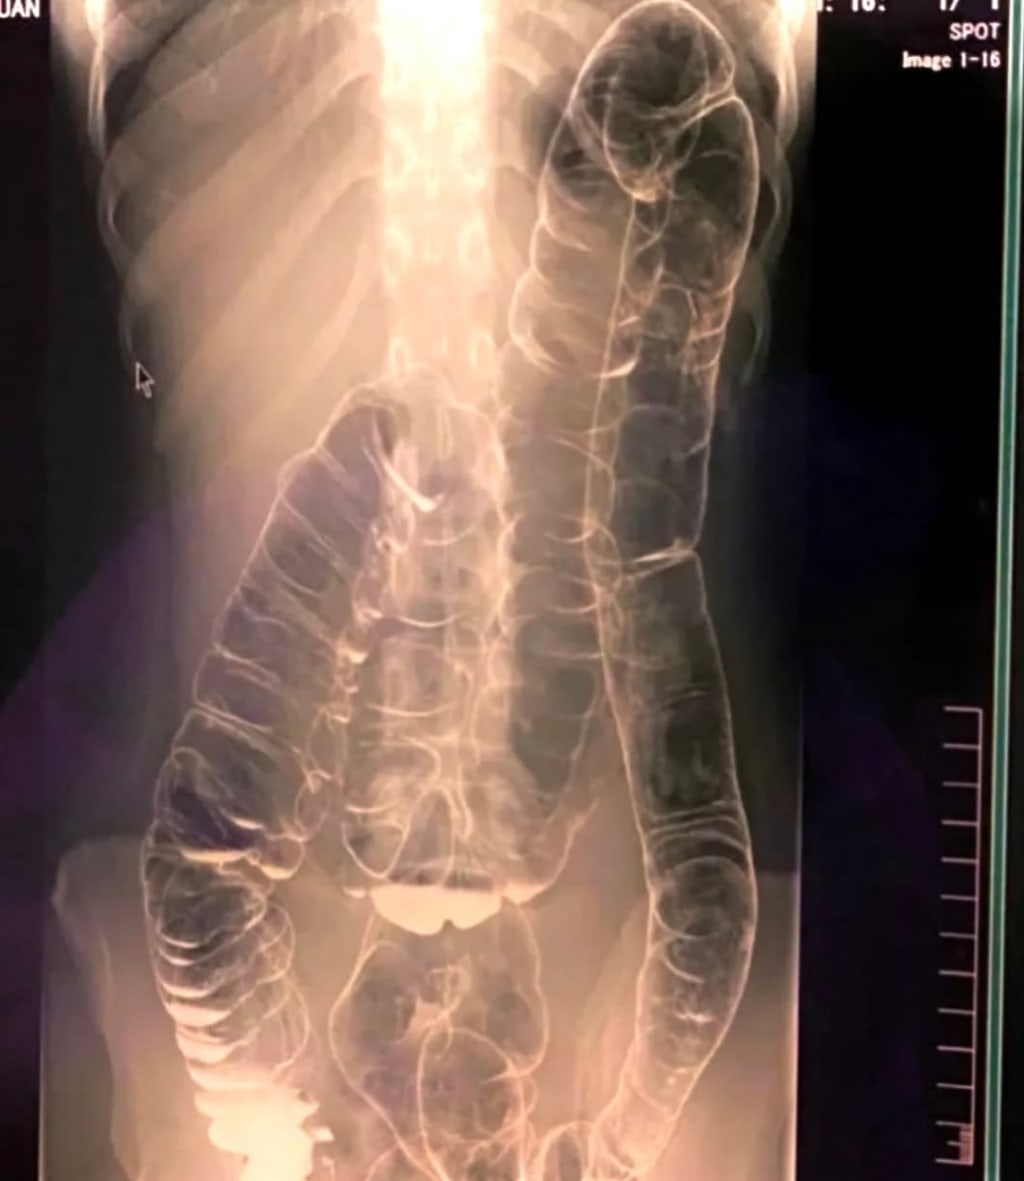

It wasn’t until day sixteen, when Lara began experiencing waves of nausea and dizzy spells, that she finally walked into an urgent care center. The attending physician took one look at her distended abdomen and ordered an abdominal X-ray.

The diagnosis: severe fecal impaction.

“I was shocked. I didn’t even know that was a thing.” Lara was treated with a combination of enemas, osmotic laxatives, and a carefully monitored hydration regimen. It took three more days—nineteen in total—before she was finally able to pass stool with some relief.